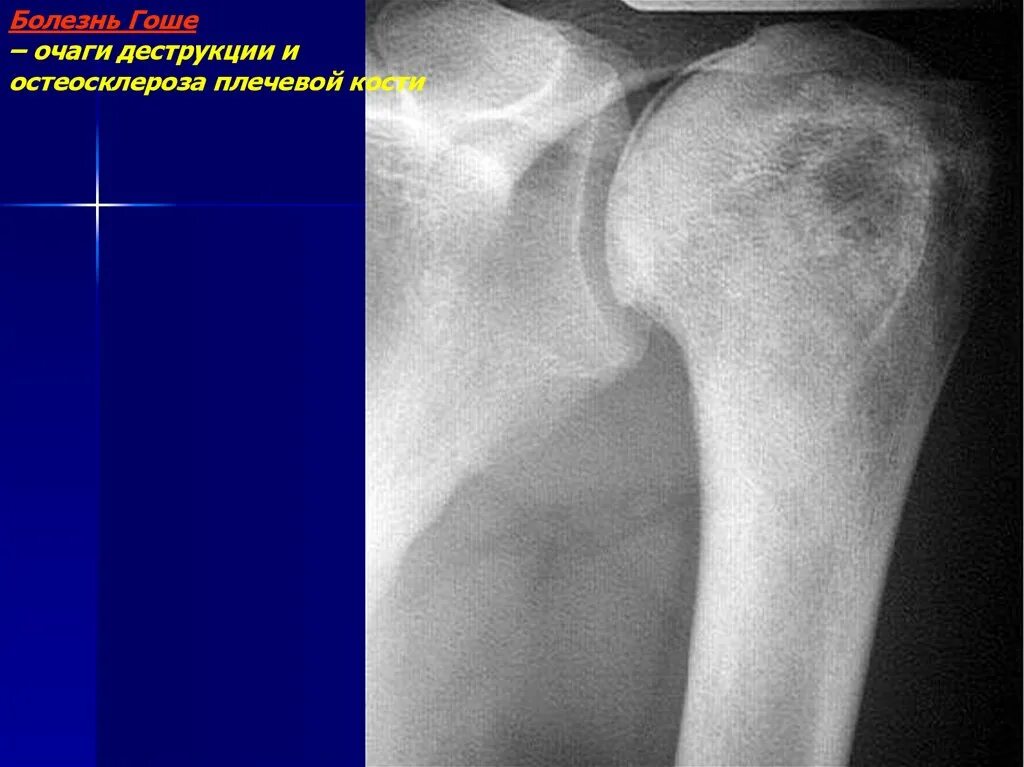

Зона деструкции